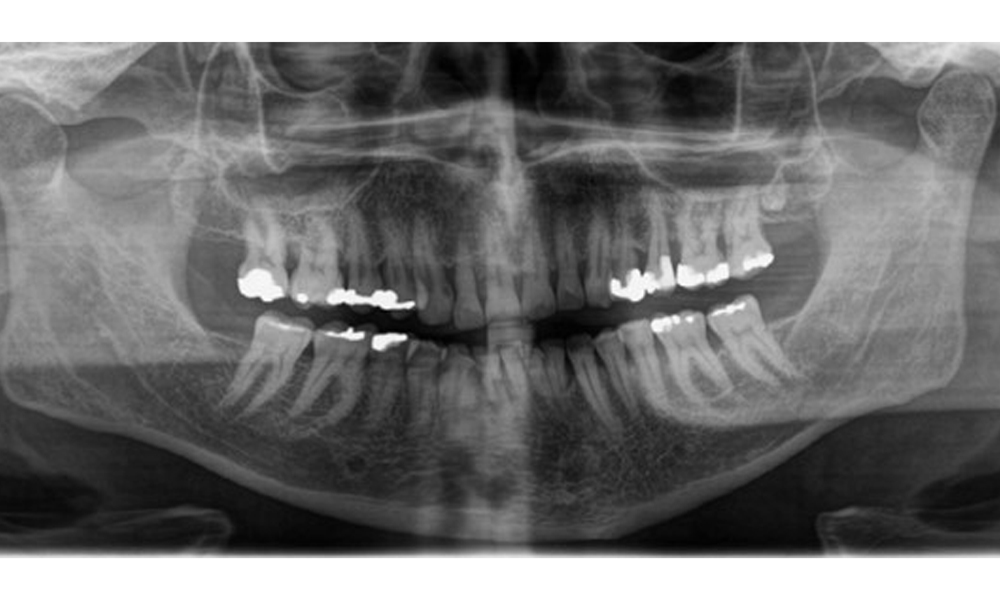

There is fully dentulous adult dentition with generalized bone loss of between 20-50% and multiple areas of vertical bone loss. Radiological examination revealed no visible caries. (Fig. 7)

Panoramic X-ray image showing generalized radiological bone loss with multiple vertical defects of between 20% to 50%.

Fig. 7 Panoramic X-ray image showing generalized radiological bone loss with multiple vertical defects of between 20% to 50%. © Dr R. Krapf